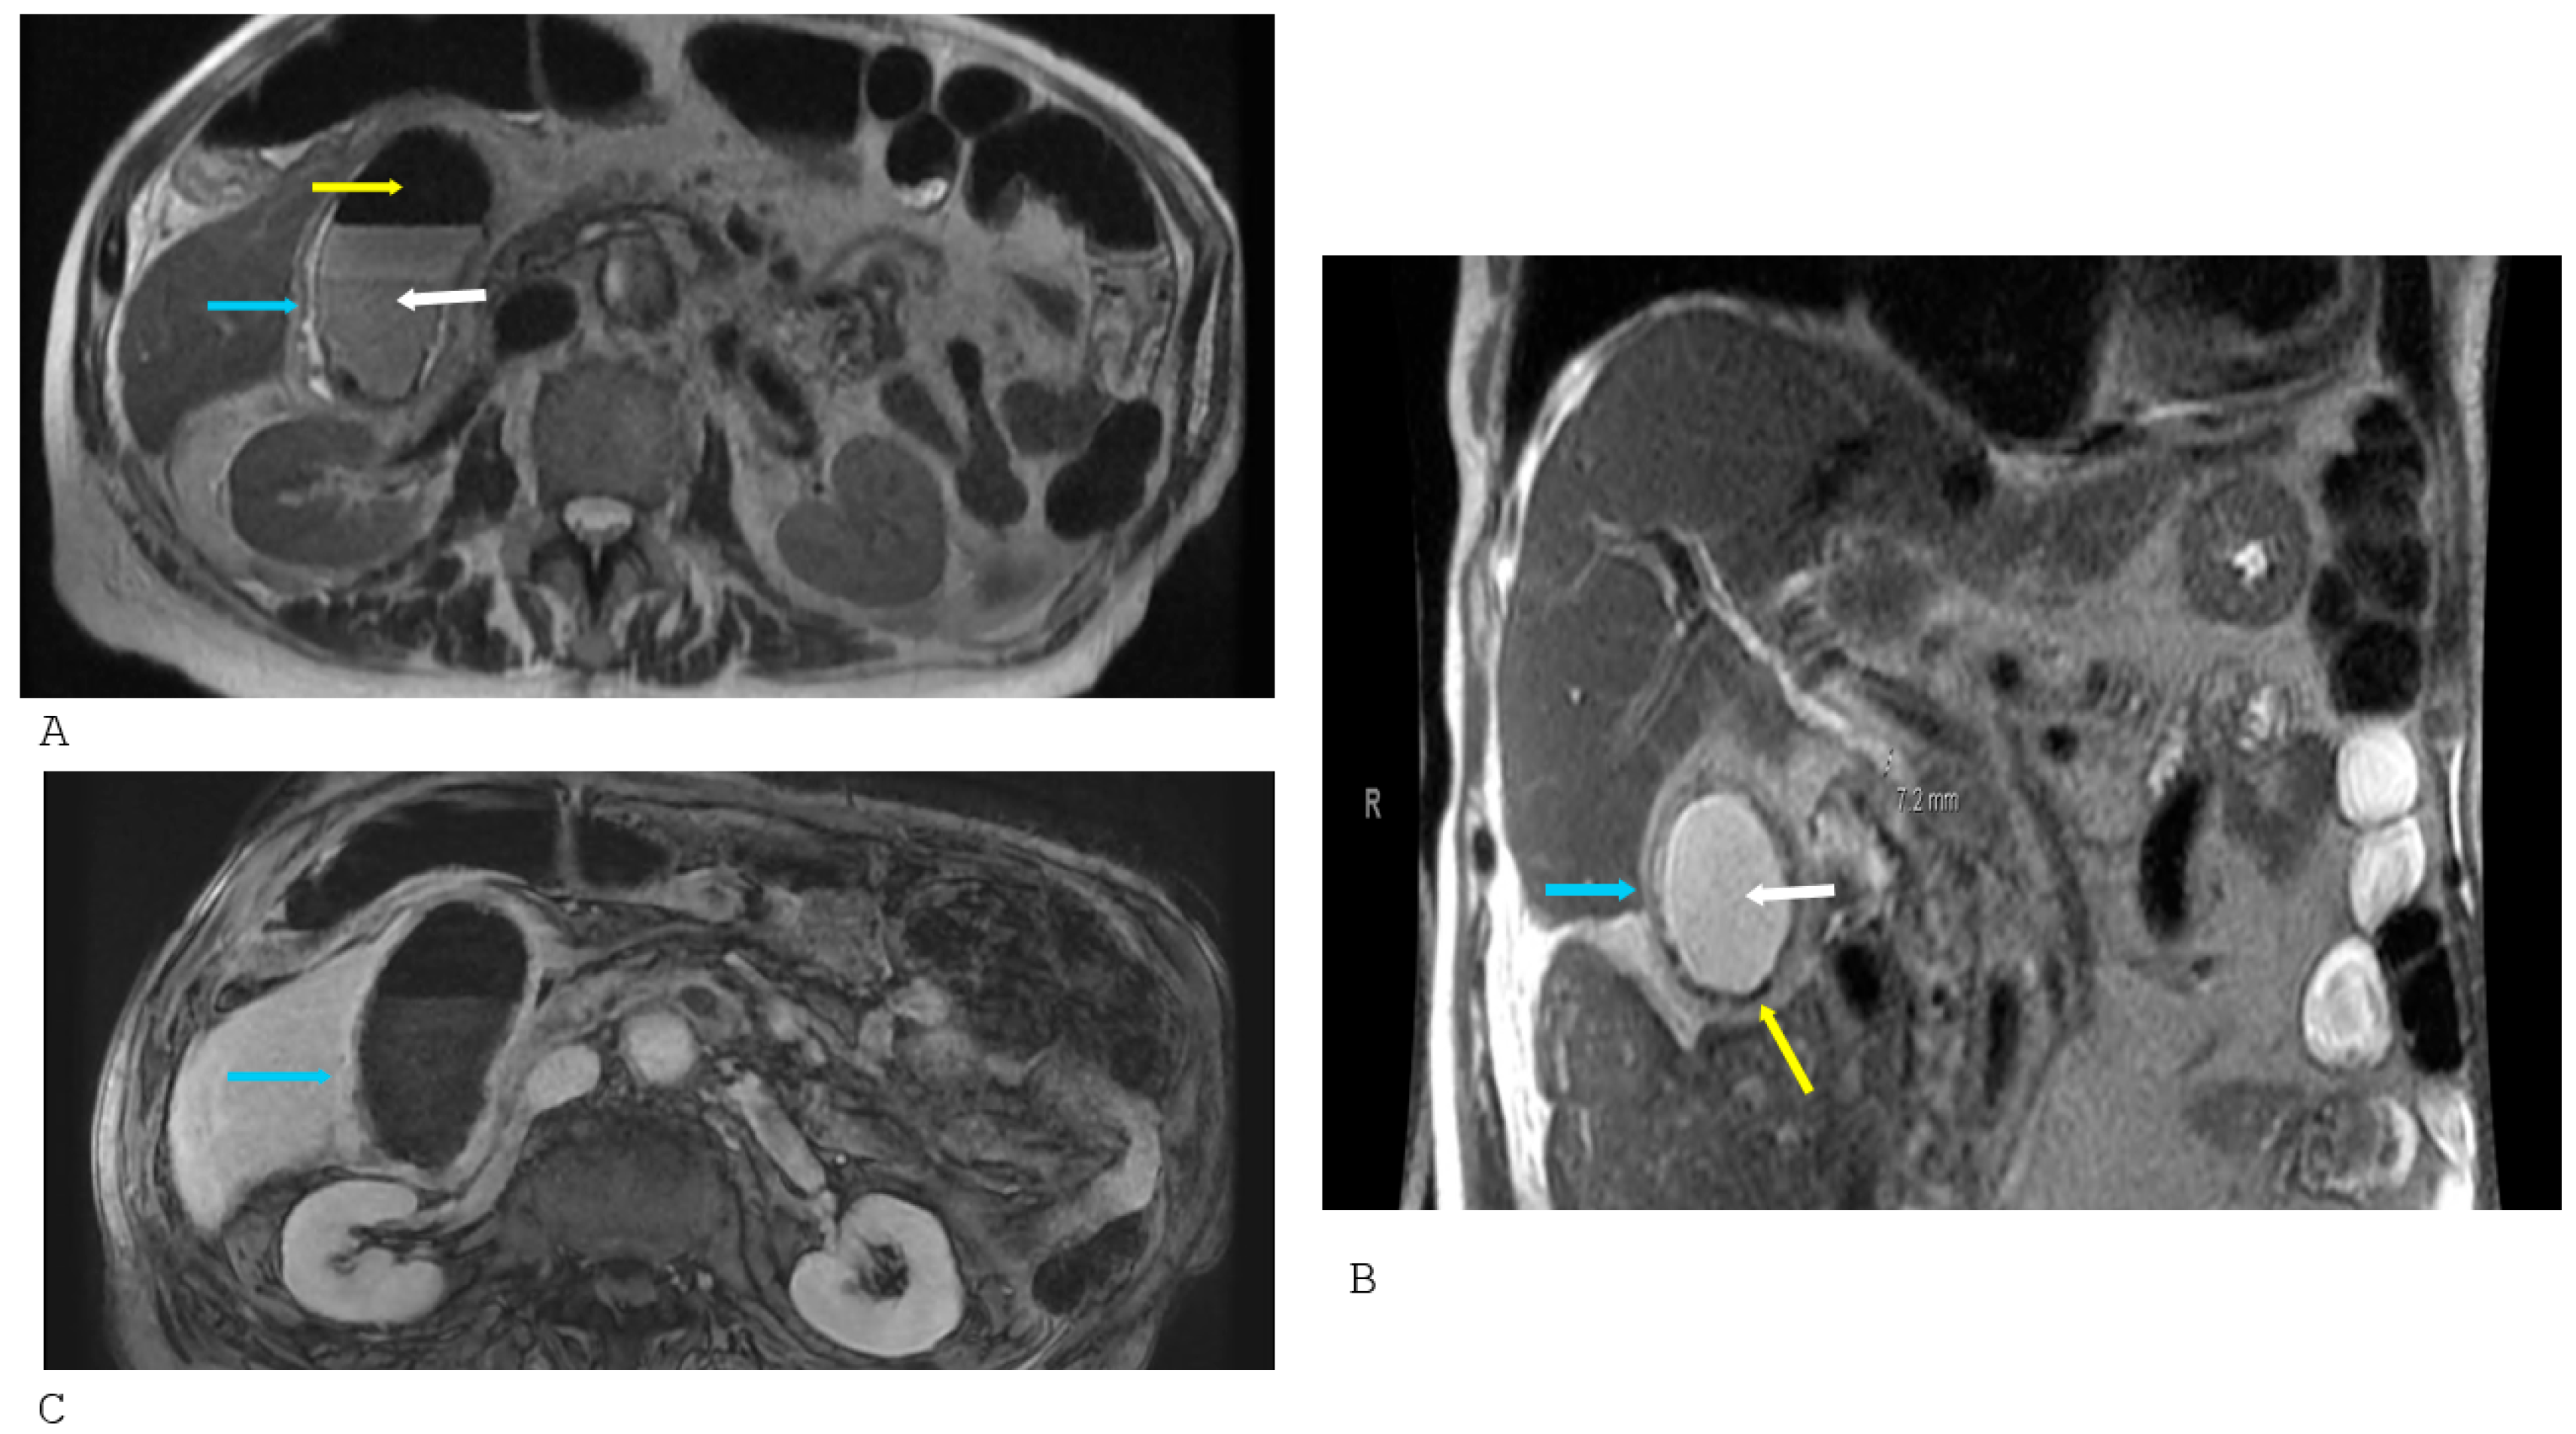

MRCP is increasingly utilized to assess suspected biliary duct obstructions, and cases of EC may be incidentally detected during these evaluations. MRCP findings indicative of EC include increased T2 signal intensity reflecting gallbladder wall edema, signal voids indicating the presence of gas, and blooming artifacts on gradient echo sequences due to gas presence [22]. Advanced sequences, including DWI, further improve sensitivity for detecting gallbladder wall inflammation, edema, and associated biliary tract involvement. Figure 6 illustrates MRI findings in a diabetic patient with EC.

Beyond conventional MRI sequences, multiparametric imaging can enhance the characterization of emphysematous cholecystitis. T1-weighted imaging may demonstrate hypointense gallbladder wall regions corresponding to edema or necrosis, while T2-weighted sequences accentuate wall thickening and pericholecystic fluid collections. Gradient echo sequences are particularly sensitive to small foci of intramural gas, which appear as signal voids and can be distinguished from adjacent vascular structures or bile. The combination of T2 hyperintensity with corresponding restricted diffusion on DWI sequences provides a non-invasive biomarker of active inflammation, allowing differentiation of emphysematous changes from chronic wall thickening or gallbladder sludge. Additionally, post-contrast T1-weighted imaging can delineate areas of mucosal enhancement versus non-enhancing necrotic segments, thereby aiding in the early detection of gangrenous transformation and informing surgical planning [22].

MRI also serves a valuable role in evaluating associated complications and comorbid biliary pathology. Emphysematous cholecystitis may coexist with choledocholithiasis, biliary strictures, or portal venous gas, all of which can be accurately assessed with MRCP and three-dimensional reconstructions. MRCP facilitates visualization of the entire biliary tree without ionizing radiation, allowing identification of ductal obstruction or secondary infection. In addition, MRI can help distinguish intramural gas from mimics such as porcelain gallbladder or intraluminal sludge, especially when CT findings are equivocal. While not a first-line modality in unstable patients during emergencies, MRI provides a comprehensive, non-invasive assessment for EC in stable patients, expanding the clinician’s ability to plan tailored interventions and anticipate complications [17].

Figure 6. Magnetic resonance imaging of a 53-year-old female diabetic patient with emphysematous cholecystitis. (A,B): Axial T2 and coronal T2 sequences demonstrate gallbladder sludge (white arrow), intraluminal gas and intramural gas signified by the gas-related signal voids (yellow arrows), and gallbladder wall edema (blue arrow); (C): Post-contrast axial sequence demonstrates mucosal hyperenhancement (blue arrow) of the gallbladder wall. The lack of enhancement of the gas-related signal voids (yellow arrows) and signal void on all sequences distinguishes them from susceptibility and flow-related artifacts, which would enhance.